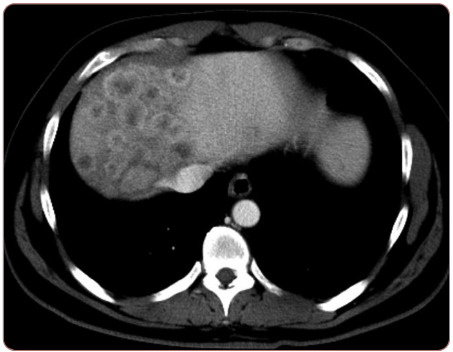

Aplastic anemia (AA) is a bone marrow failure disorder resulting in peripheral pancytopenia and marrow hypoplasia. An alternative diagnosis of hypoplastic myelodysplastic syndrome (MDS) can overlap this diagnosis but is differentiated by the presence of dysplastic progenitor cells. Since AA can be characterized as an autoimmune disease directed against hematopoietic stem cells, its presence can potentially increase susceptibility to alternate malignancies. Hypoplastic MDS, however, can present itself in an extramedullary fashion solely or as a relapse of acute myeloid leukemia resulting in symptoms similar to those described in this case study. Solid tumor malignancies may also result in abnormal blood counts, creating a wide differential diagnosis. This manuscript presents a case of untreated AA in a patient presenting later with severe abdominal bloating.